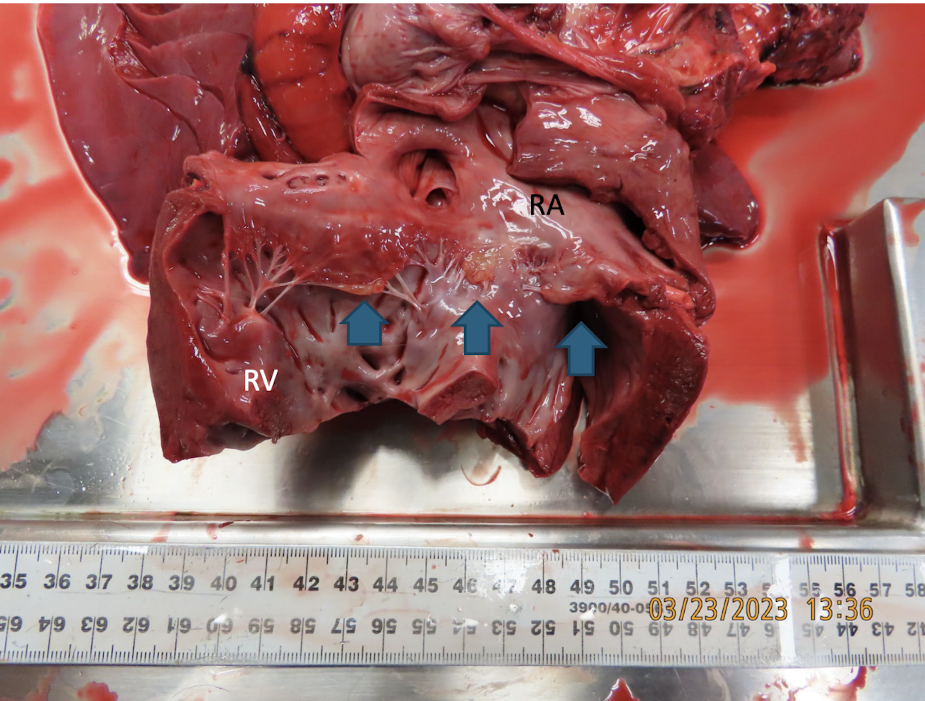

<p>What is this showing?</p>

What is this showing?

tricuspid/mitral valvular dysplasia